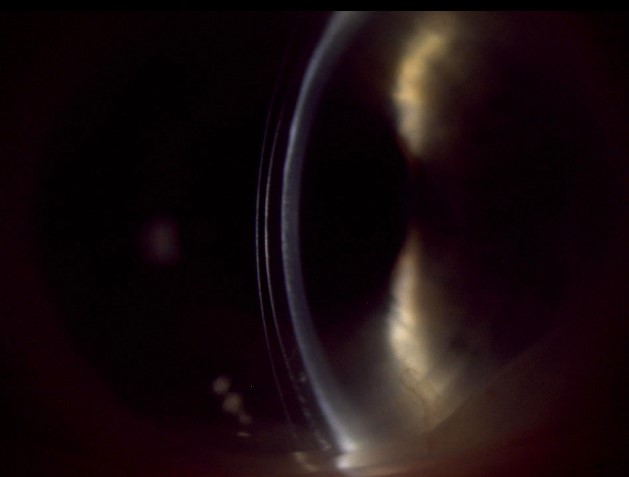

Figures 2a and 2b: View of anterior segment OD/OS: Sparse lashes of upper and lower eyelids, inflamed lid margins and bulbar conjunctiva, and subepithelial scarring of the central cornea with accompanied thinning.

Figures 3a and 3b: Slit lamp view of scleral lenses OD/OS with optic section demonstrating adequate fluid reservoir clearance over areas of scarring and thinning.